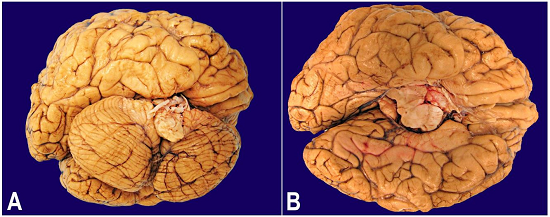

Significant findings at autopsy included poorly differentiated gastric adenocarcinoma (Figure 3A) metastatic to left supraorbital dura, pituitary gland, pericardium, lungs with evidence of lymphangitic carcinomatosis, liver, peripancreatic soft tissue, mesentery of large bowel, wall of colon, bilateral periadrenal soft tissue, thoracic vertebrae, periprostatic soft tissue and urinary bladder. Additionally, the pericardium, peritoneum, peripancreatic soft tissue, periadrenal soft tissue, perithyroidal soft tissue, laryngeal soft tissue, periprostatic soft tissue, small and large bowel and subdural soft tissue surrounding the spinal cord showed mucoid material containing distended cells with foamy cytoplasm and eccentric nuclei (Figure 3B and 3C), consistent with a mucopolysaccharidosis. Other notable findings at autopsy were persistence of fetal lobulation in each kidney, severe malrotation of brainstem and cerebellum (Figure 4A and 4B) and thinning of optic chiasma and left optic nerve.

Another notable finding in the current case was persistent fetal lobulation in the kidneys, which represent a normal variant reflecting incomplete fusion of the developing renal lobules. The kidney function is essentially normal, however, the ultra-sonographic findings in such kidneys may be mistaken as scars.13 To our limited knowledge, this finding has not been described in patients with Morquio syndrome. Lastly, the brain examination of our case also demonstrated a severe malrotation of brainstem and cerebellum. However, the patient did not have any neurologic deficit in 30 years of life. It is highly likely that this malrotation was related to odontoid hypoplasia and could very well be a protective mechanism against brainstem and spinal cord compression, which is common complication of odontoid hypoplasia in Morquio patients.